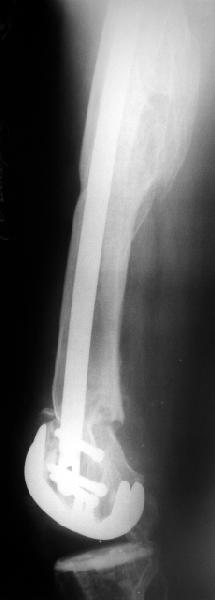

Глубокоуважаемые коллеги, Мужчина 41 года поступил с повторным (предыдущий в 2001 г.) переломом (3-недельной давности) над протезом коленного сустава.

A male 41 years old transferred to our unit with 3 week old femoral fracture near the knee prosthesis after a mimimal fall. In 1994 he sustained multiple injury with open patella fracture (complicated with septic arthritis), and ipsilateral femoral shaft fracture treated by ex-fix. TKA performed in 1998. In 2001 he got a periprosthetic fracture which was treated nonoperatively and healed with ~1 cm dorsal displacement of the distal femoral block. Knee ROM prior the recent injury was about 90-95 degrees. He didn't use walking aid.Images attached. I request your suggestions regarding surgical options in the situation? We mostly discuss ante- vs retrograde closed nailing.

В итоге сделали антеградный остеосинтез. В дистракторе свежий перелом вправился сразу, а вот старый - оставил проблему, дистальный отлмомк остался все равно кзади. И гвоздь бы прошел кпереди от него, а ретроградный - перфорировал бы передний кортекс. Так что пришлось еще сделать чрескожную остеотомию через перелом, чтобы малость мобилизовать дистальный отломок. Снимки в прилжении.

The radiographs look excellent and a good outcome would be anticipated. The idea to osteotomize the femur shaft to compensate for the prior shaft malunion was clever and should work fine.

I can't actually see the osteotomy on either radiograph. Is it more proximal than we see in these radiographs or so well aligned as to be not visible?

Отправитель: Alexander Chelnokov 02 Июнь 2004, 13:58

The osteotomy was perfromed trough the fracture site. See the image.